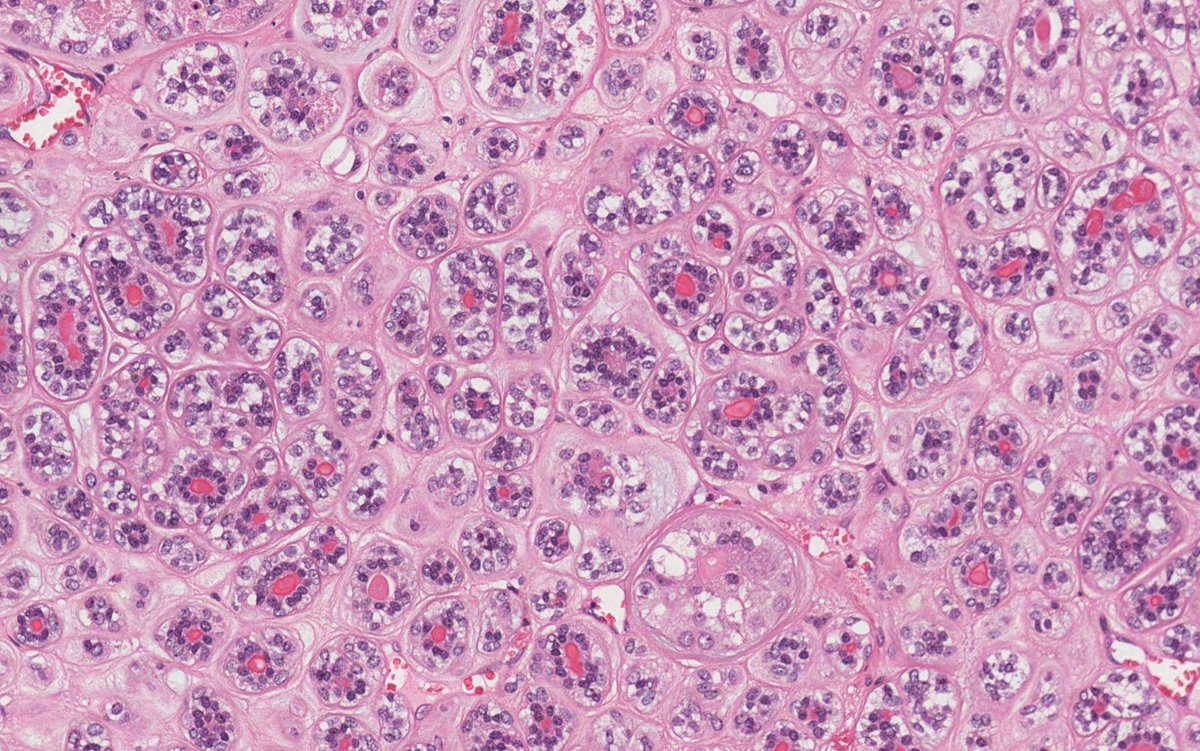

70M with parotid mass. What is your diagnosis? #oralpath #oralpathology #pathology #pathologists #pathTwitter #HeadNeckPathol #HeadandNeckPath #ENTPath #PathologyTweet

70M with parotid mass. What is your diagnosis?

This is epithelial-myoepithelial carcinoma, a rare salivary gland malignancy showing biphasic tubular structures with inner ductal and outer clear myoepithelial cells. Often harbors HRAS Q61 mutations, CK7+ luminal and SMA/p63+ abluminal cells, with favorable prognosis.